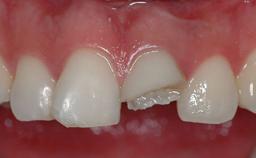

The patient presented with a failing tooth-supported fixed dental prosthesis with cantilever extension replacing the right maxillary central incisor. His chief presenting complaint was poor esthetics, in particular the dark discolored margin around the abutment tooth, the maxillary left central incisor. He reported a history of trauma at a young age, which necessitated the replacement of his maxillary right central incisor as well as root canal therapy of the adjacent left central incisor. The existing prosthesis had been in situ for over 20 years. The initial periapical radiograph displayed good proximal bone levels at the adjacent teeth and a wide incisive canal, which was a concern. The left central incisor presented a very wide root canal treatment with compromised radicular dentin thickness, which was a consideration in the decision between a new tooth-supported fixed dental prosthesis vs. an implant-supported prosthesis. After a lengthy discussion on the risks and benefits of both treatment options, the patient decided on a single-tooth implant replacement.

Soft Tissue Contour and Volume Slightly compromised